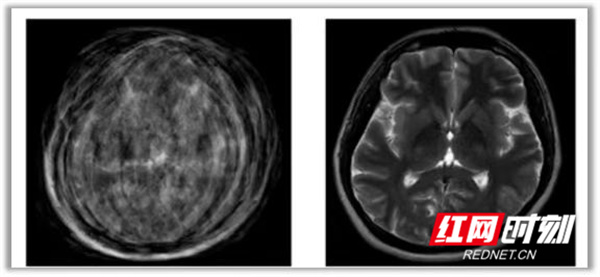

左侧为运动是扫描成像,右侧为正常成像。

磁共振检查噪音大、时间长,检查环境陌生,一些小朋友容易产生恐惧心理,清醒状态下难以保持身体静止,这会使检查图像产生运动伪影,影响诊断结果。因此,对于新生儿、年龄较小或无法配合的儿童,通常需要药物镇静和剥夺睡眠等护理干预,来配合检查。而选择最佳的镇静时间,是磁共振检查成功的关键。